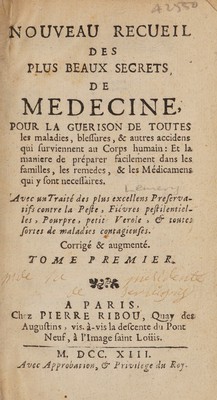

Nouveau recueil des plus beaux secrets / Corrigé & augmenté. [Anon].

- Louis Lémery

- 1713

Credit: Nouveau recueil des plus beaux secrets / Corrigé & augmenté. [Anon]. Source: Wellcome Collection.